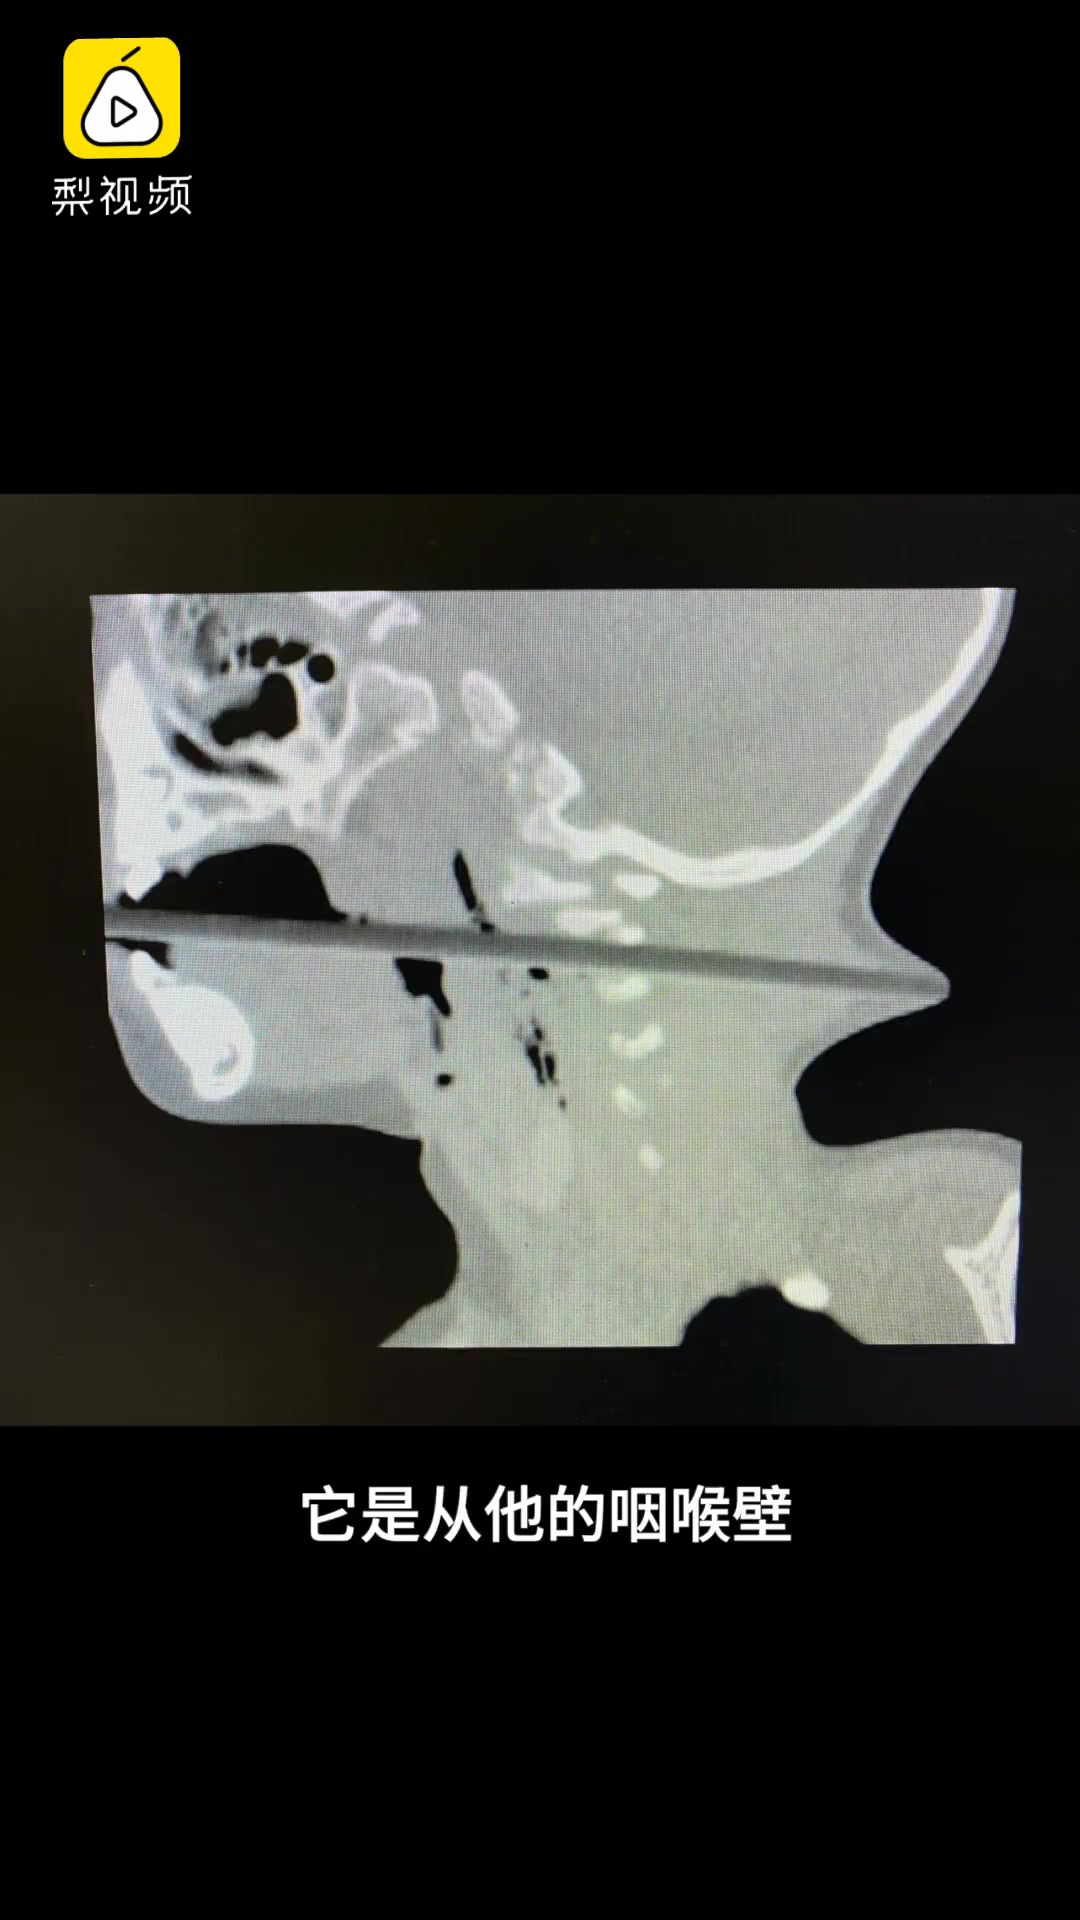

2岁男童持筷子插入喉咙近15公分,靠近动脉险些丧命

男孩吃饭时不慎滑倒筷子直插喉咙 差点贯穿后颈

生命垂危的孩子被送至遵医附院抢救,3个小时的手术后,筷子才被取出.